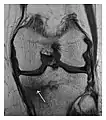

The sacrum is usually masked by overlapping bowel gas in conventional radiographs, and the subtle radiographic findings are usually nondiagnostic and even misleading. The characteristic "H" pattern has been correlated with biomechanical models of patient activities. The vertical parasagittal planes correspond to the region of maximal stress during walking, while the horizontal fracture develops later, secondary to the loss of lateral support by parasagittal fractures. MRI is the primary imaging technique in this case, with the most common MRI pattern showing bone marrow edema and a fracture line (Figure 12). Coronal views are quite contributive in sacral fractures, allowing the detection of the horizontal component, especially with fluid-sensitive sequences. Although the sacrum is the most commonly involved, pelvic insufficiency fractures are often multiple, and other typical locations should be mentioned.[1]

Proximal femoral fractures usually occur in osteoporotic patients, and their signs include subtle neck angulation, trabecular angulation, and subcapital impaction line. A frog-leg lateral view may be helpful if the greater trochanter is short enough. However, positioning can be difficult because of hip pain. In patients with strong suspicion of proximal femoral fracture and negative radiographs, MRI limited to coronal T1 W images and scintigraphy can be highly valuable (Figures 13 and 14). Such an option, with limited examination time, is cost-effective and allows reliable exclusion or confirmation of the diagnosis, preventing an unnecessary stay at the hospital or delayed treatment. Moreover, MRI helps to detect soft tissue abnormalities which are more frequently seen in femoral, acetabular, and pubic injuries than sacral lesions. Concomitant fractures are also frequently seen in typical pelvic sites.[1]

a

b

Figure 13: Partial osseous avulsion of the gluteal muscles at the greater trochanter in a 59-year-old man who presented with the right hip pain without a history of trauma. Lauenstein view and anteroposterior and radiographs (not shown) did not show an obvious fracture line or disruption of bony contours in the acetabulum or the right femoral neck. (a) Coronal T1-weighted MRI displays an incomplete fracture line extending partially from the greater trochanter (arrow). (b) Coronal short tau inversion recovery MRI shows heterogeneous hyperintensity in the same region (arrow) as well as hyperintensity within the gluteus medius and minimus muscles (arrowheads) consistent with tissue edema and hematoma.[1]

Figure 14: Subcapital insufficiency fracture in a 55-year-old man with a left hip pain without a history of trauma. Anteroposterior and Lauenstein view radiographs centered on the left hip do not show an obvious fracture line, but mild acetabular osteophytosis was noted consistent with hip osteoarthritis (not shown). (a) Coronal T1-weighted MRI shows a linear low-signal band through the femoral neck corresponding to a fracture line (arrowheads). (b) Bone scintigraphy shows focal uptake (arrow) corresponding to the fracture.[1]